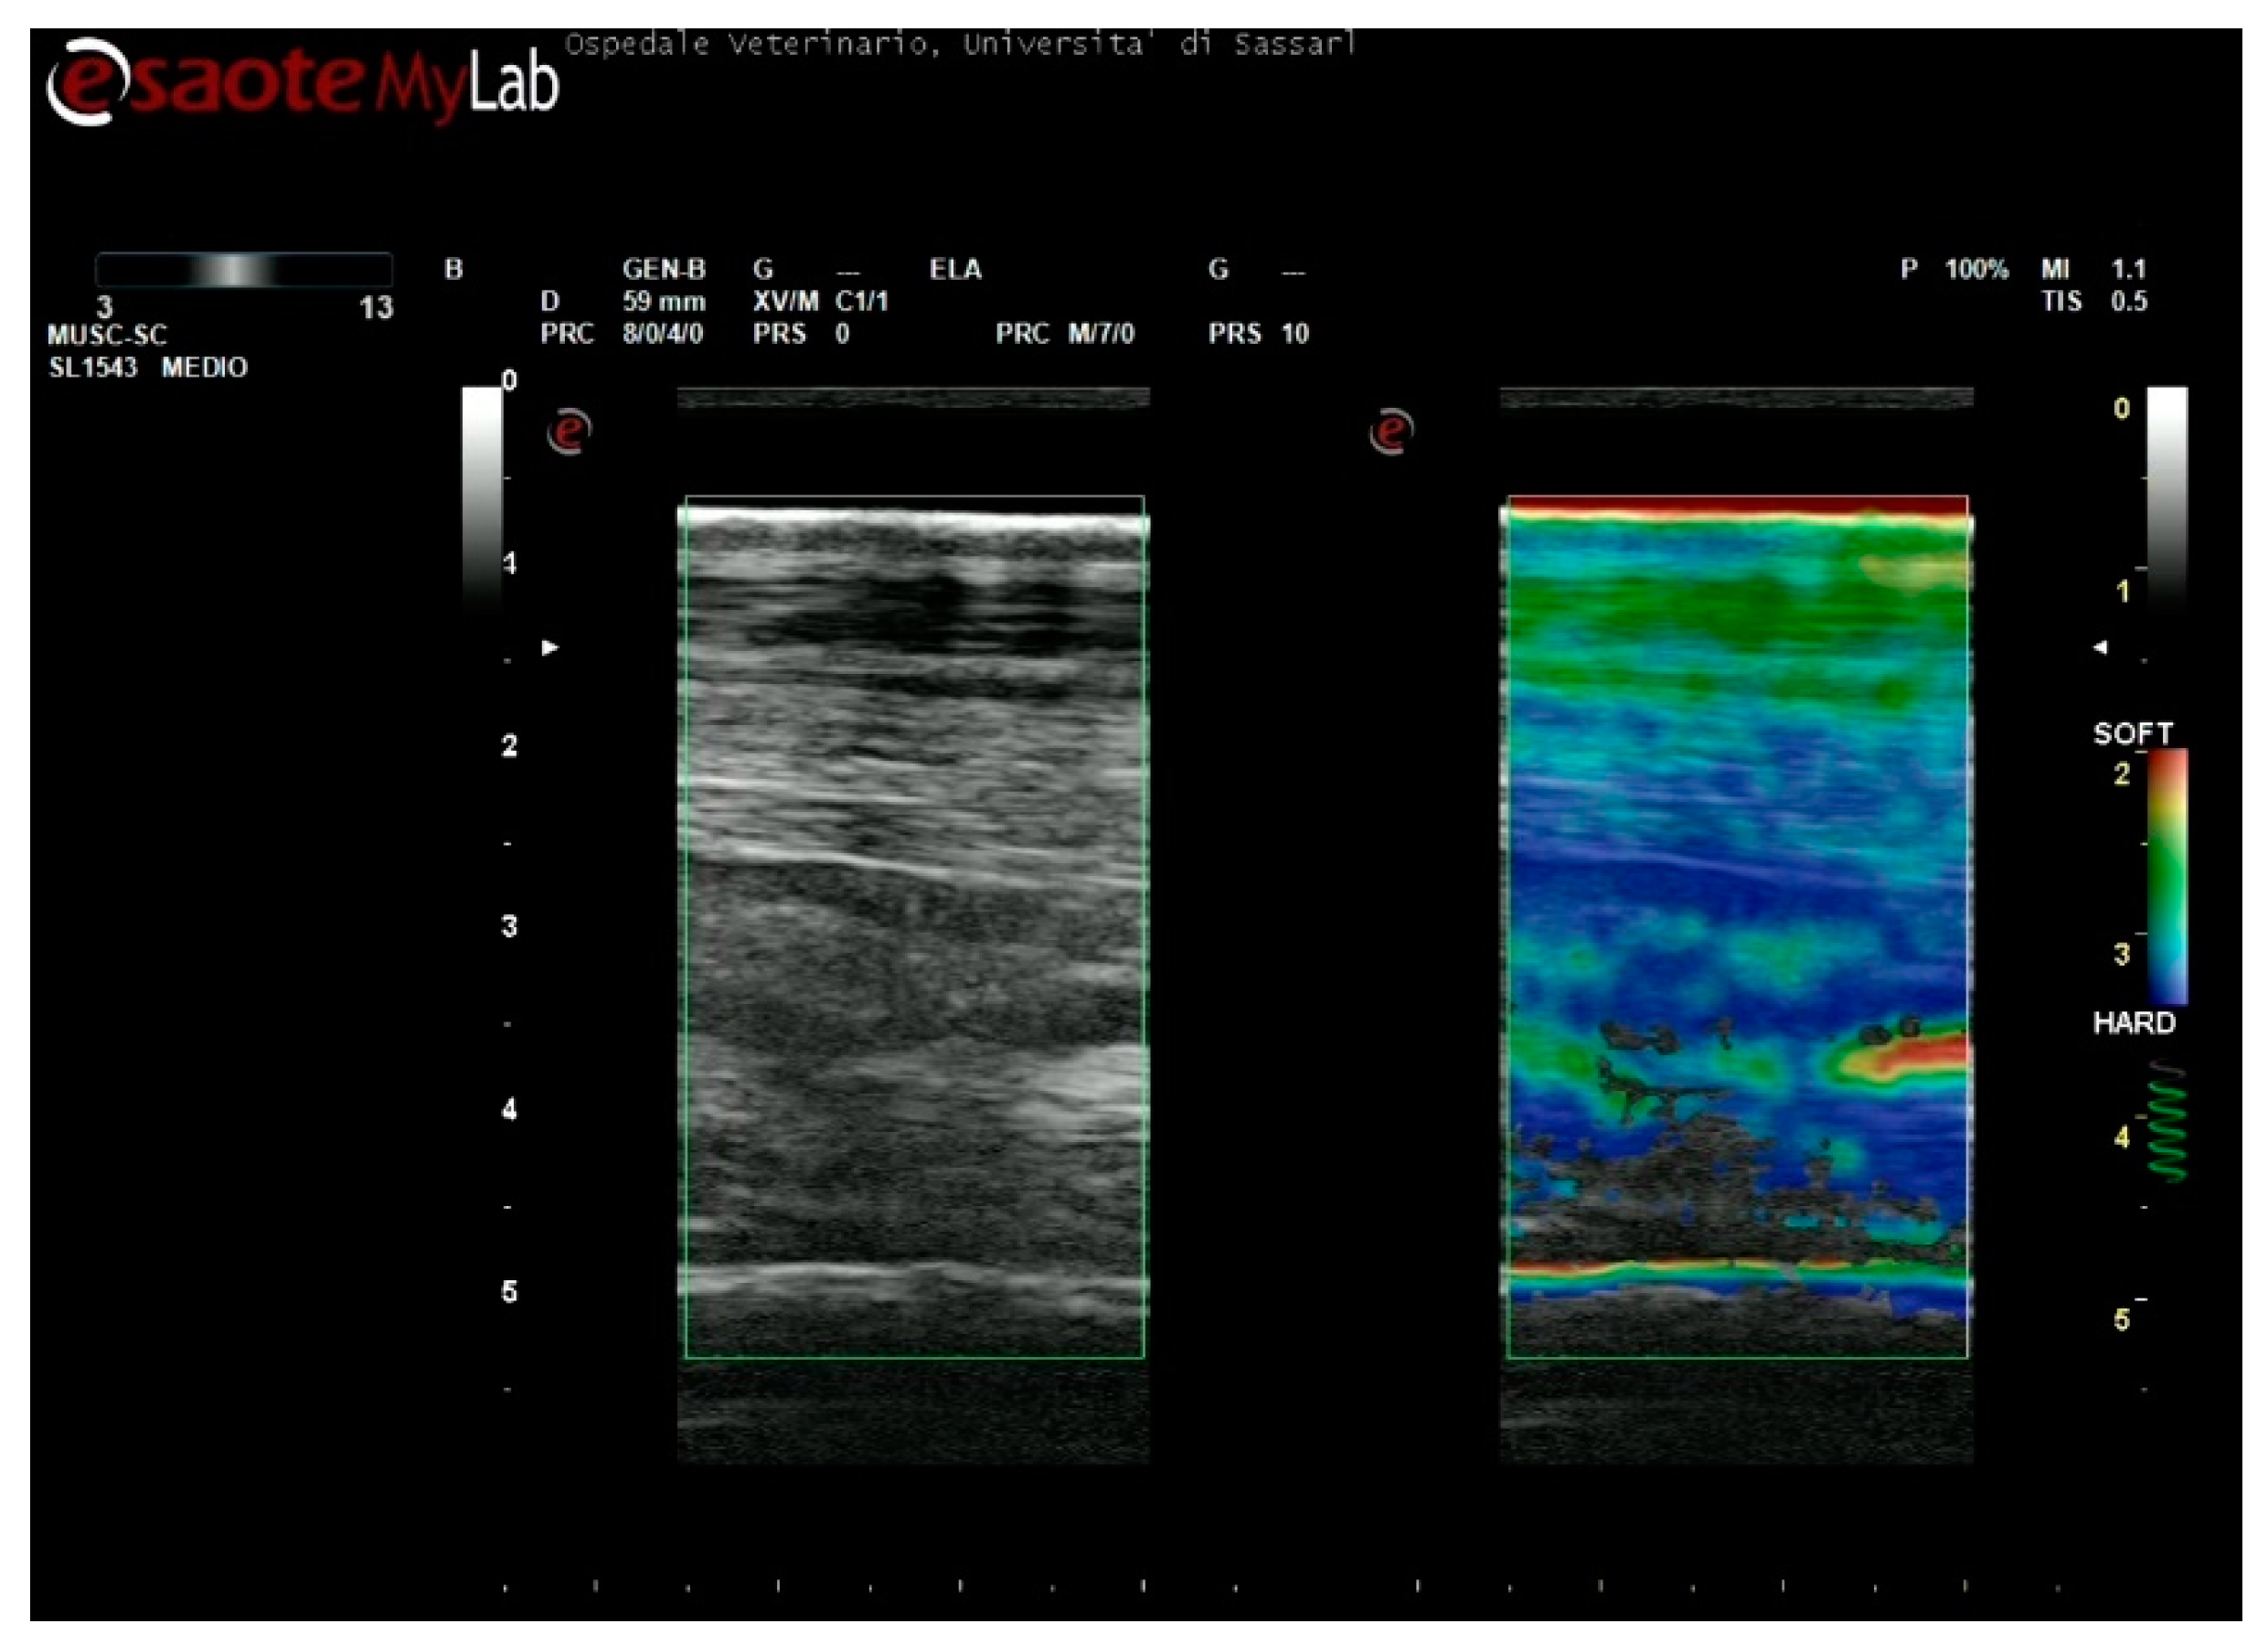

A color-coded map was selected, with a range of red (softer tissues) through yellow/green (intermediate stiffness) to blue (stiffer tissues) colors.

The accuracy of the elastograms obtained was evaluated during the examination by checking a visual indicator. As the correct compression was applied, the indicator color changed from grey to green, and a videotape was recorded for each level of the metacarpus (Figure 1).

Figure 1. Example of strain elastography. (A) Color range selected, (B) Indicator for correct compression, (C) Field of view.